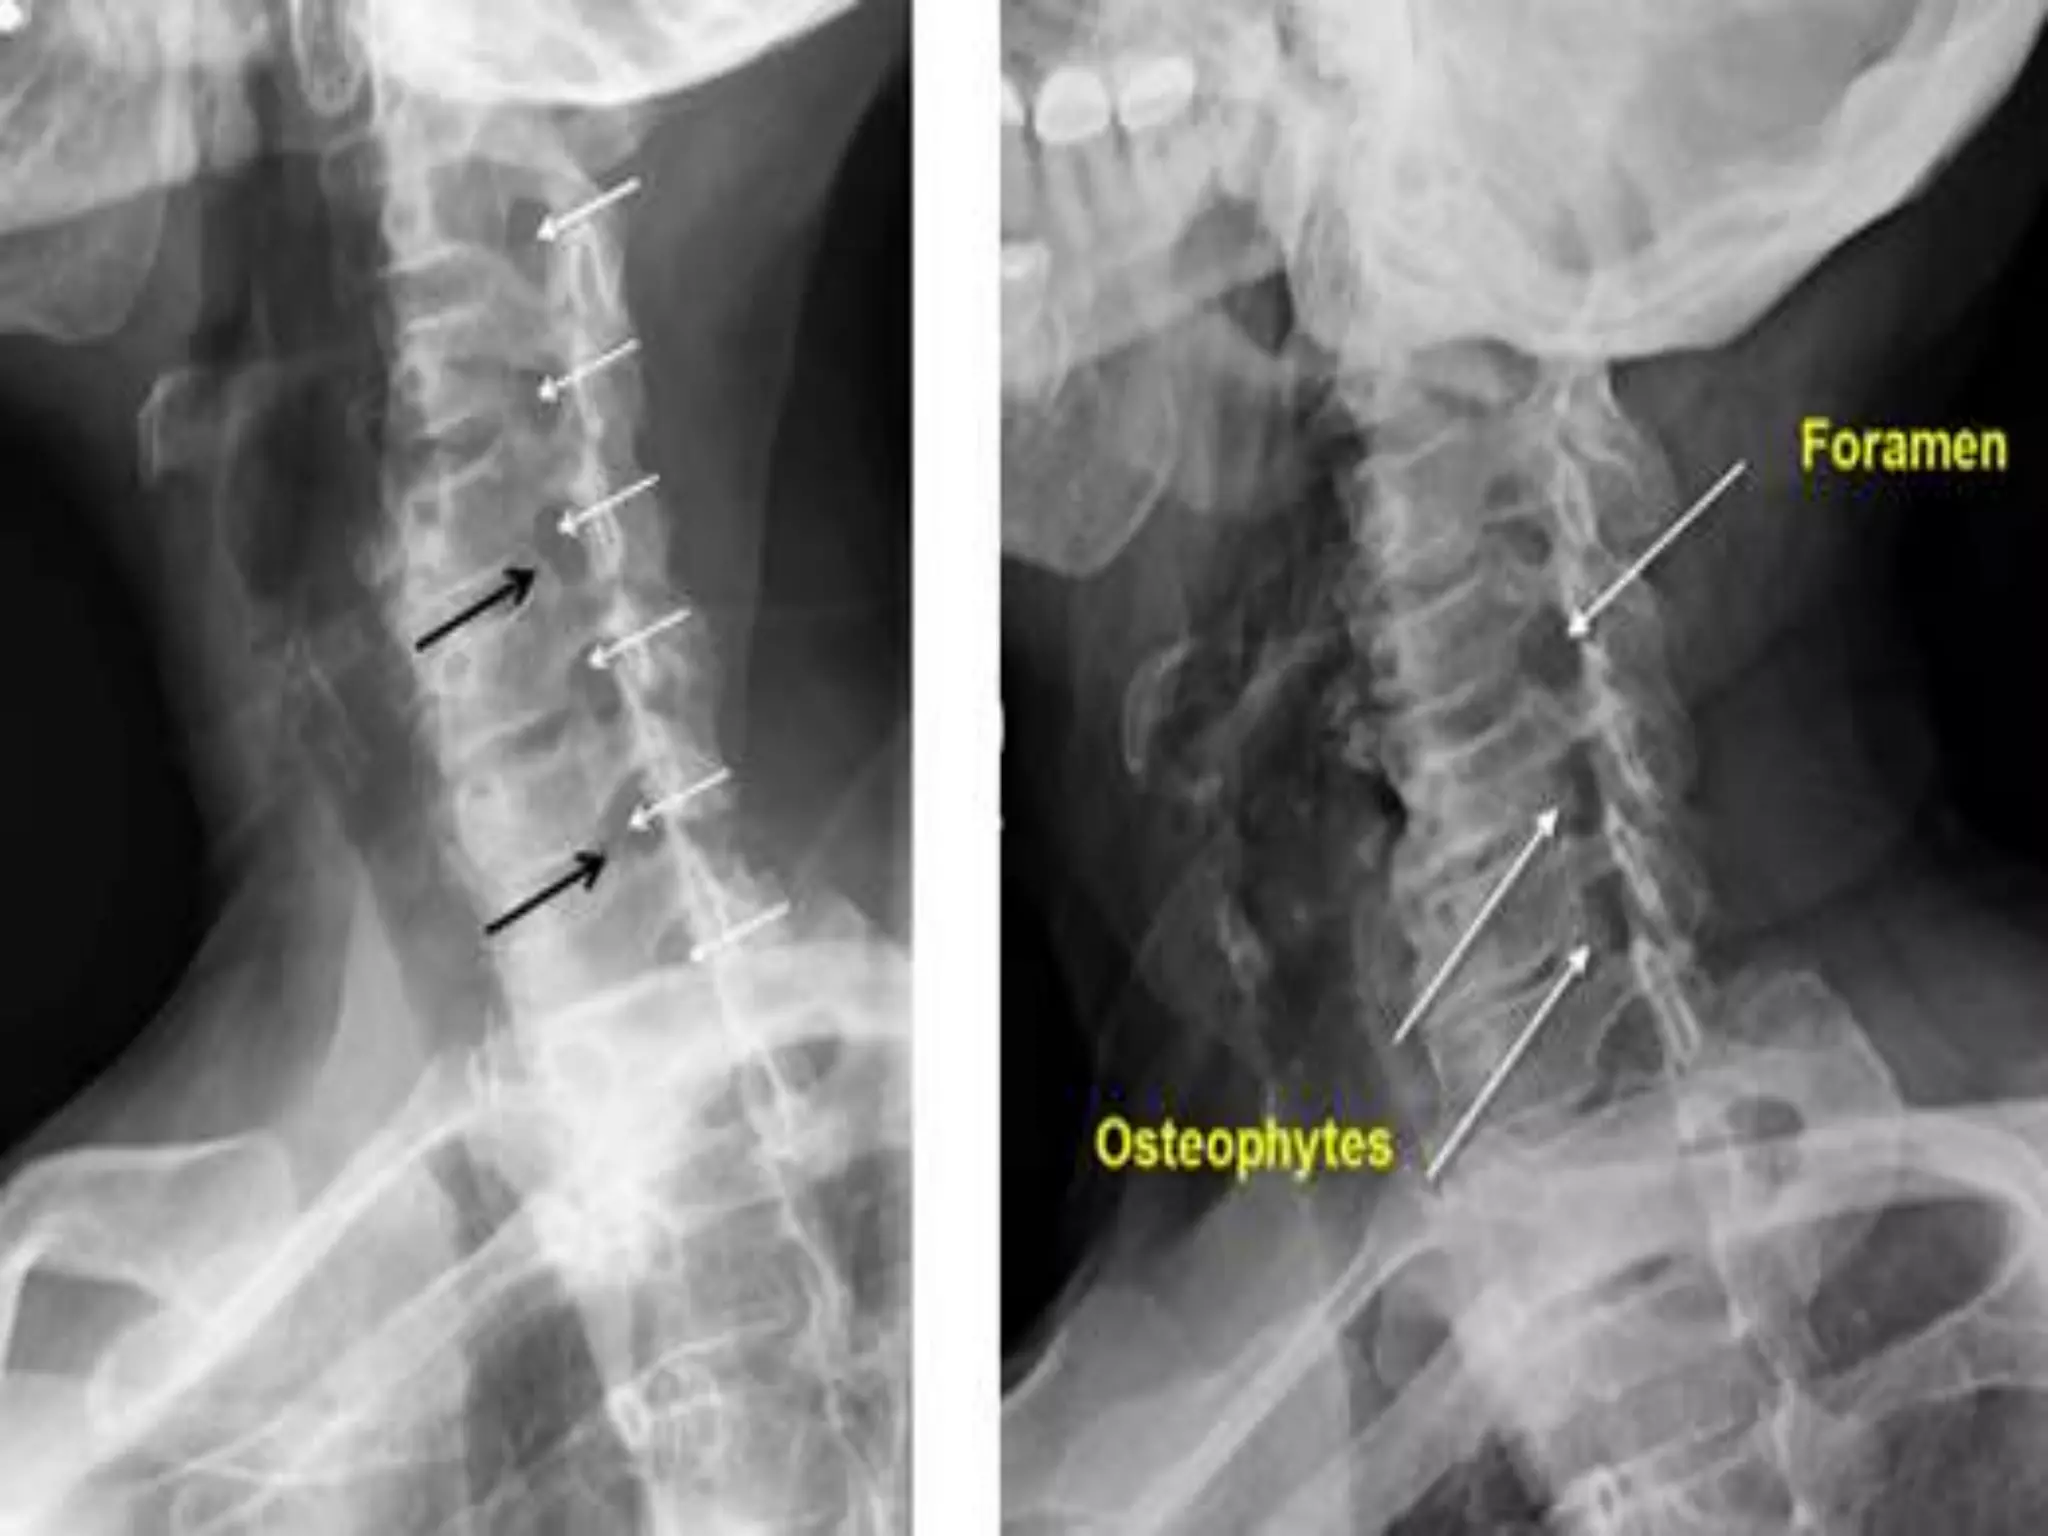

Normal AP and Lateral Views.

Thoracic Spine - AP & Lateral View.